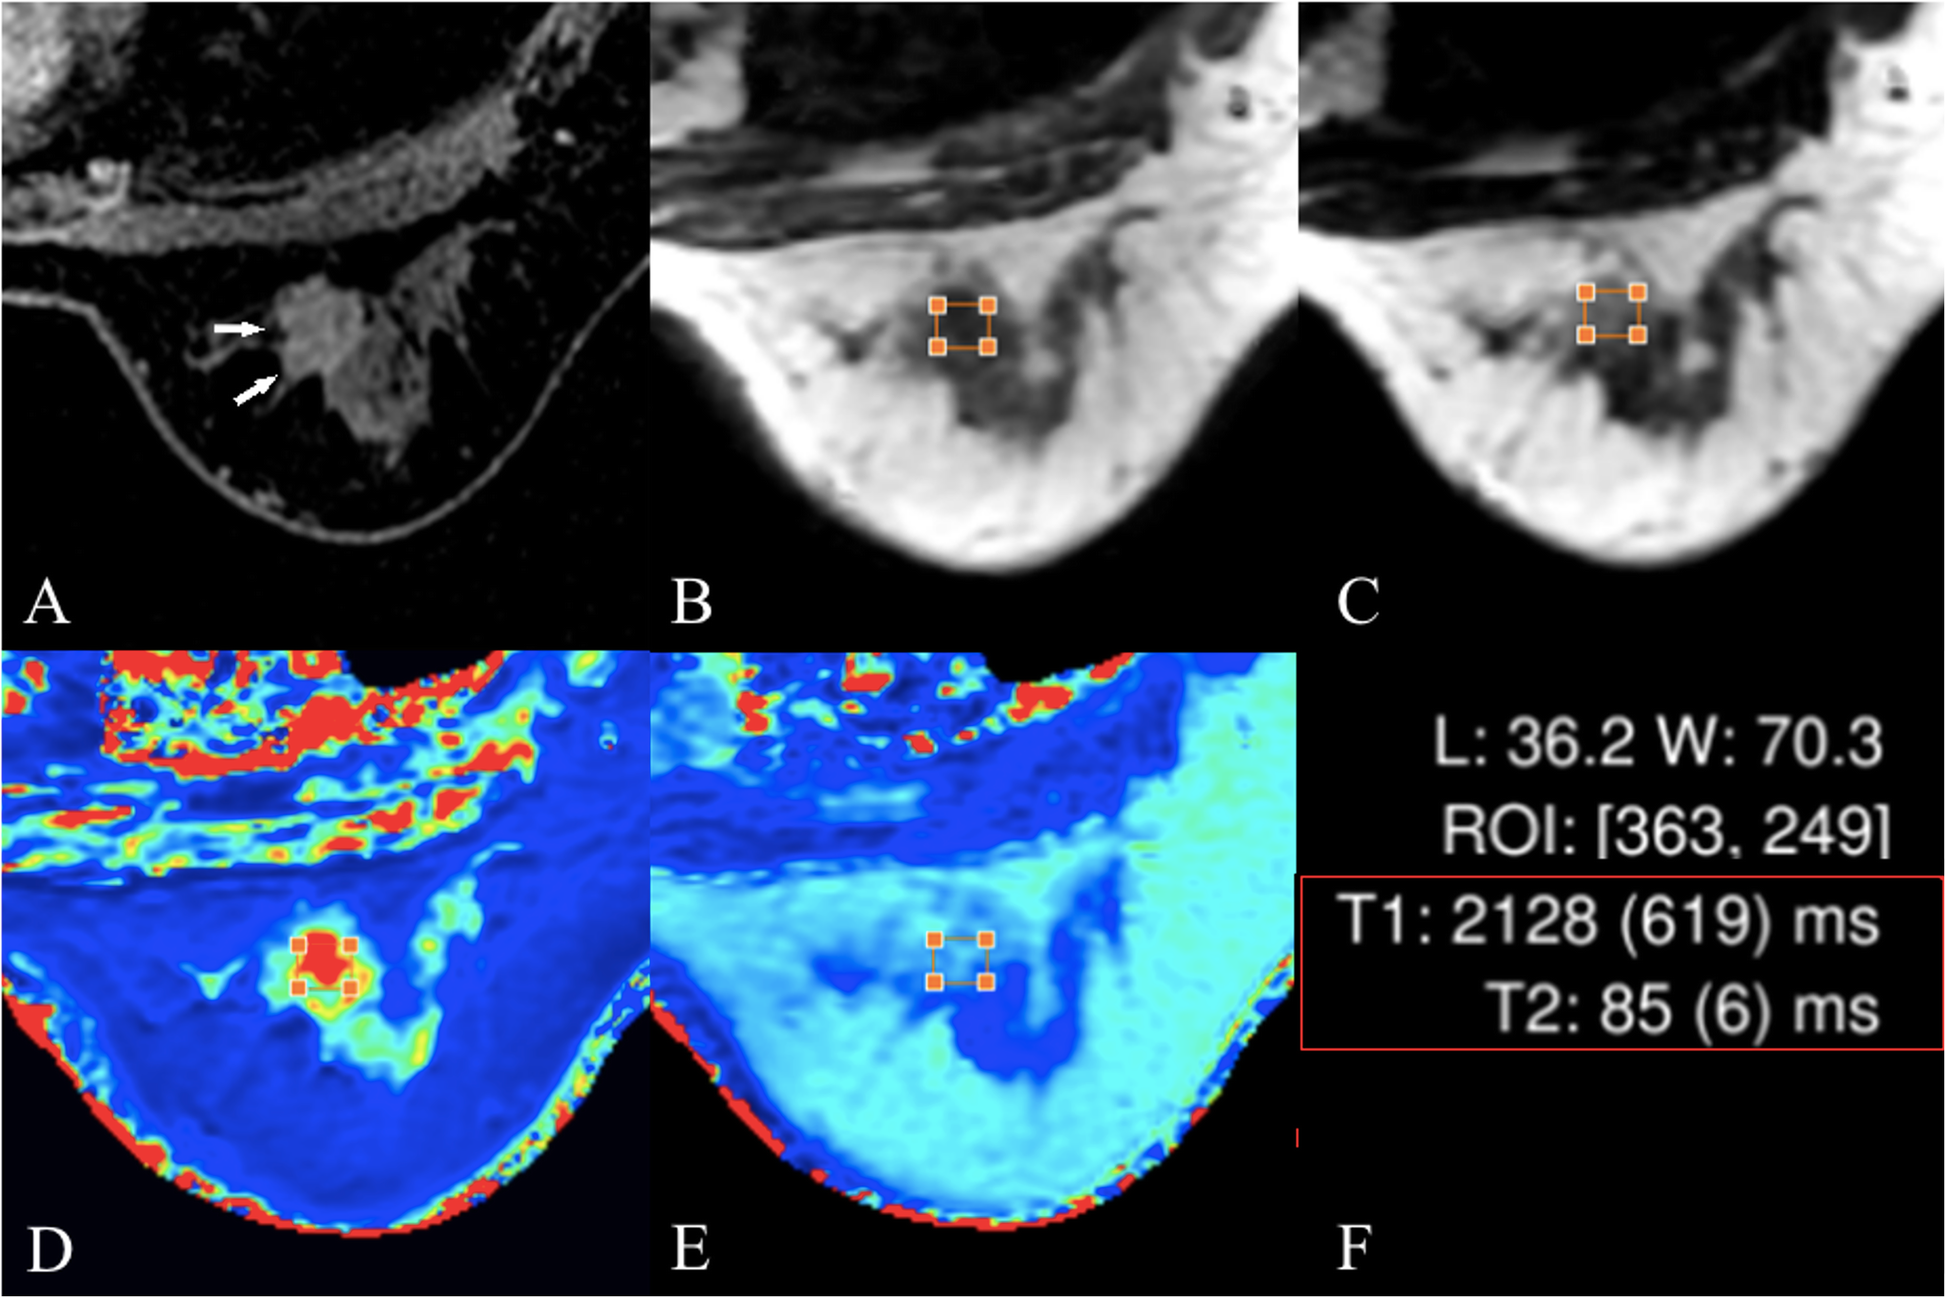

Fig. 3

Female, 42 years old, invasive ductal cancer. a the lesion is shown using white arrows in the perfusion-enhanced image; b and c, T1- and T2-weighted images obtained from SyMRI respectively; d and e, T1 and T2 maps, respectively. The T1 and T2 values are shown in f